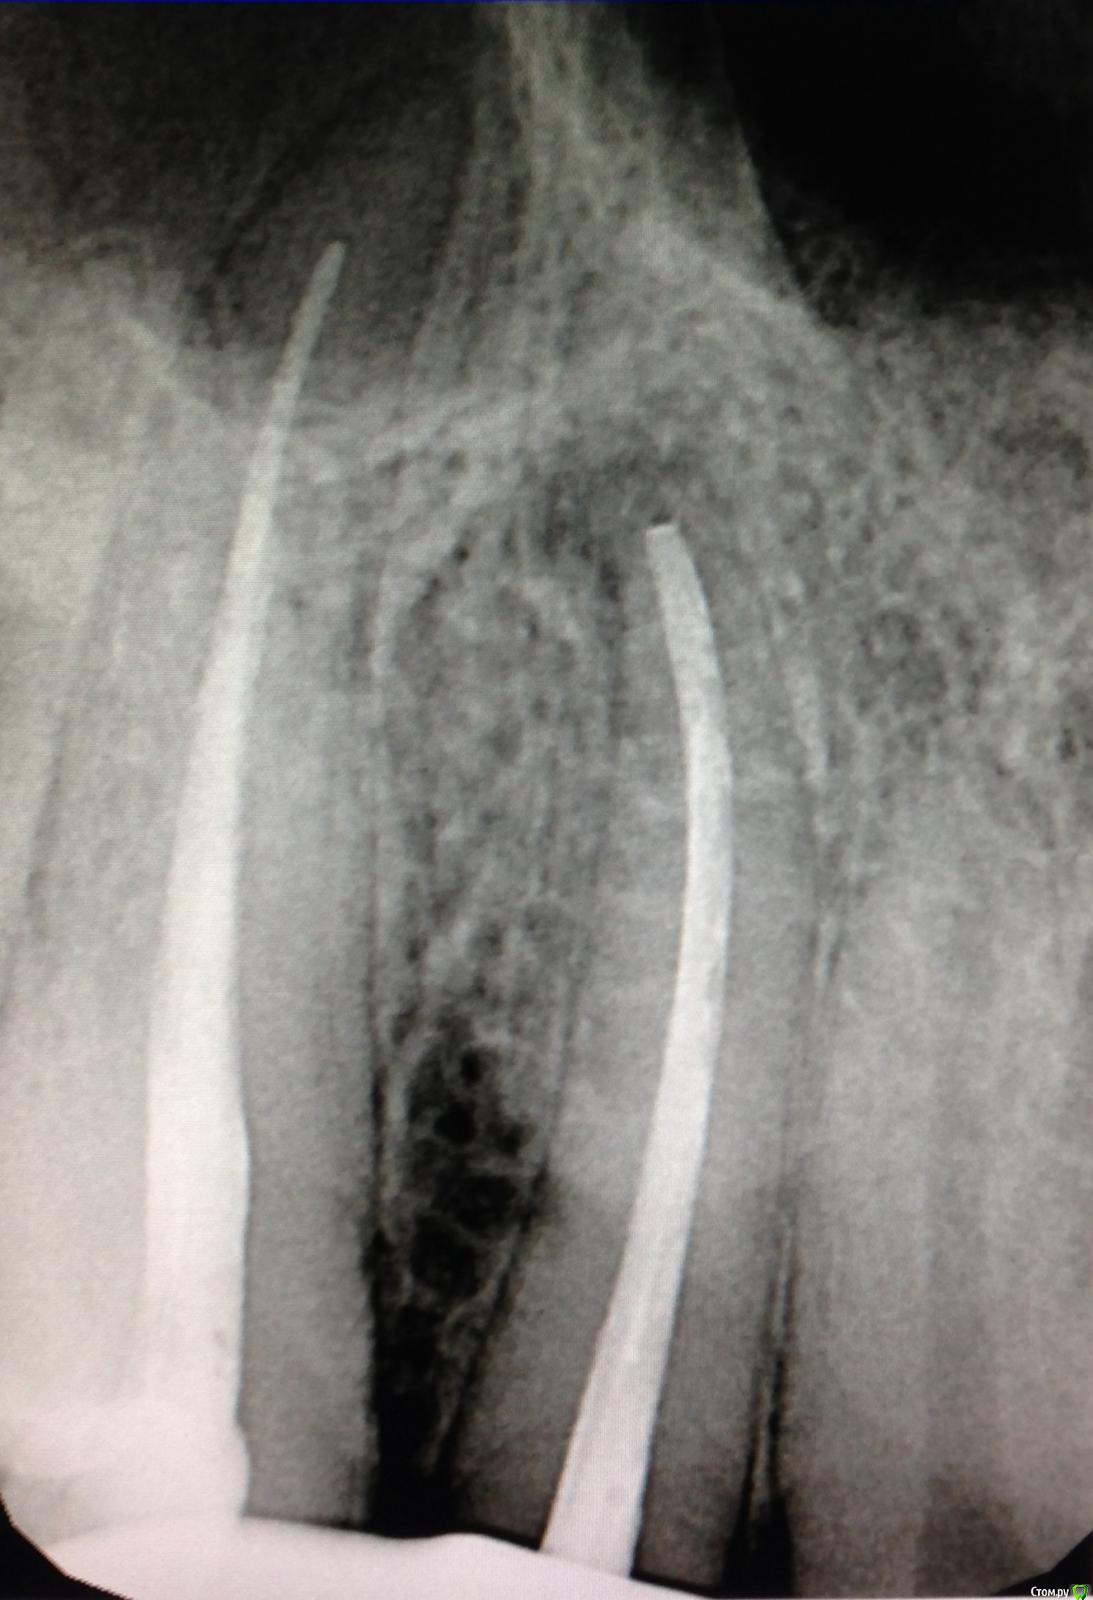

SSTi Опубликовано 9 декабря, 2014 Автор Поделиться Опубликовано 9 декабря, 2014 Чуть обновимся. Пульпитный 36. Медиальные профайлы 35.04. Дистальный 40.04. ОХАП 37. Резорцин старый. Через кальций. 12 хап. 13 пульпит. 60 упор 5 Ссылка на комментарий

SSTi Опубликовано 12 декабря, 2014 Автор Поделиться Опубликовано 12 декабря, 2014 Еще 1 пульпитный красавчик Ссылка на комментарий